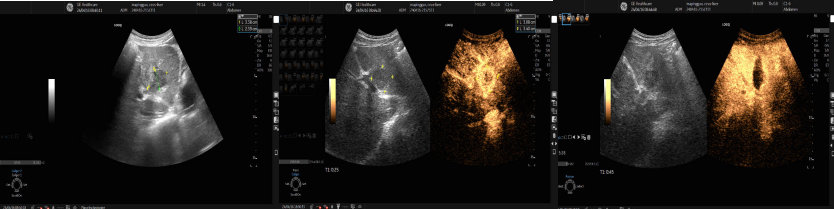

魏教授在进行超声引导下经皮肝脏肿瘤射频消融术

肿瘤科病区一名68岁的患者胰腺肿瘤术后肝脏转移,肿瘤位于肝脏S3段,大小31x30mm,被门静脉左外支上段、左外支下段及左支矢状部三面包绕,穿刺风险较高,经魏炜教授严谨会诊及精准规划定位,完美避开肿瘤周围血管,采用功率120W,累计用时10分钟完成射频消融,消融后即刻超声造影显示消融范围完全覆盖原肿瘤区域,解除了患者疾患,且整个过程患者无明显不适,实现了微创治疗。